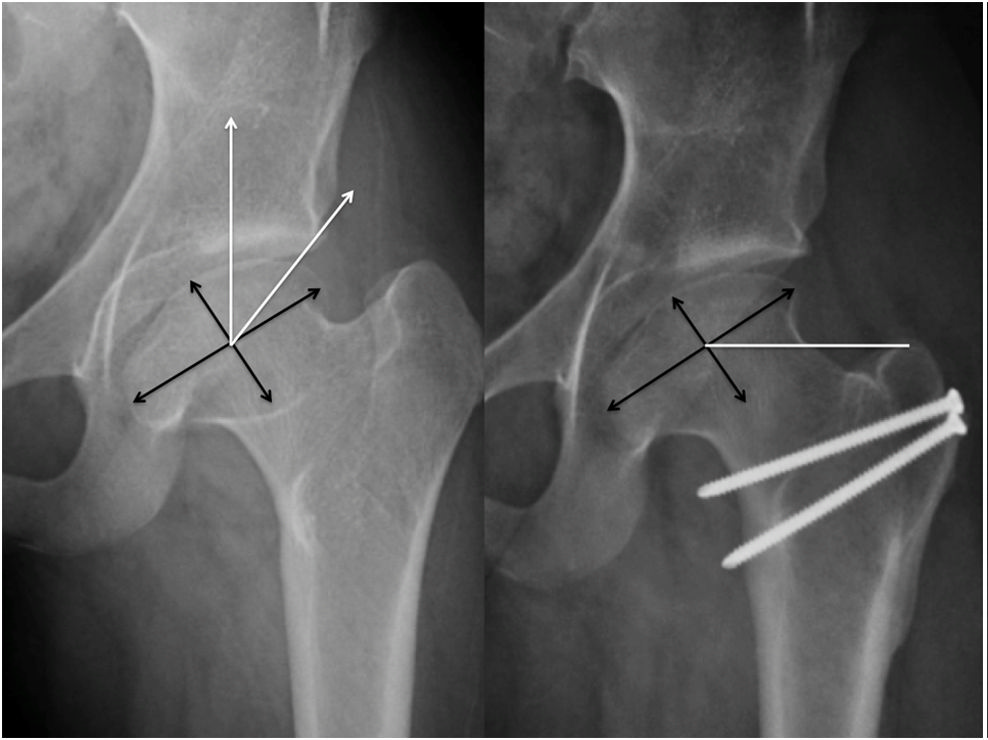

儿童特发性股骨头坏死:perthes病后遗症:髋关节外科脱位和股骨颈相对

图片尺寸988x740